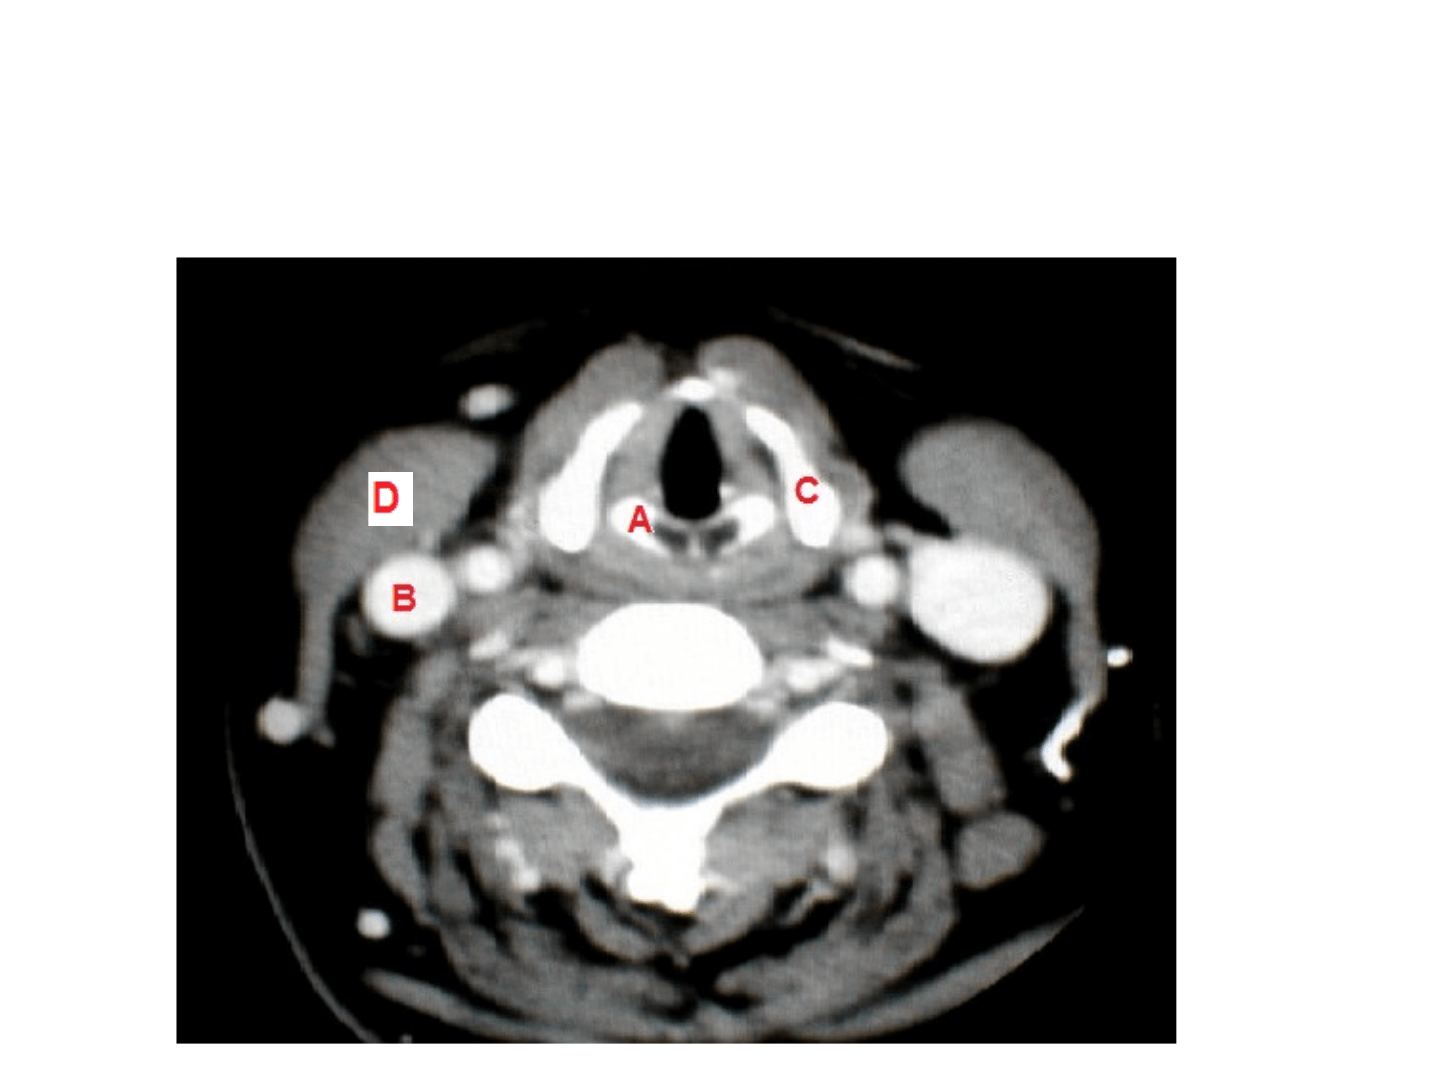

A: Cartíl

ago arit

enoides Der

echo.

B: V

ena yugular in

t

erna Der

•

C: Cartí

lago tir

oides.

D

. E

CM der